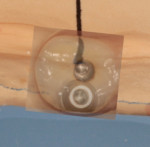

After extensive clinical and radiological examination, the treatment plan developed for the patient called for creation of a complete maxillary denture and a screw-retained permanent hybrid mandibular bridge. To retain the mandibular denture, four CAMLOG implants (CAMLOG, www.camlog.com) were placed in the mandible. Following the placement of the implants, impressions were taken and sent to the dental laboratory. From the impressions, master casts were created and mounted on an articulator (Candulor CA II, Candulor ). The condyle path inclination of the articulator was adjusted to 28º on the right and 30º on the left in neutral occlusion (Figure 1).

The mandibular restoration must be accessable between the implants for cleaning with interdental brushes. The ovate pontic on the soft tissue should not display any saddle-like constellations (ridge laps) and must be cleanable with dental floss. The denture would be mounted on an implant bar with passive bonding on the framework.

Minimal space was given at the base and between the ovate pontics to allow the patient to easily use dental floss and proxabrush (Figure 42).